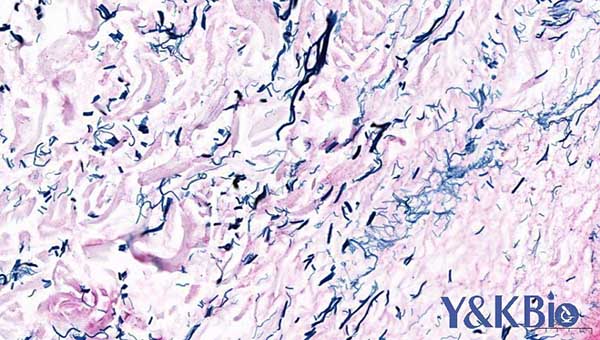

八、网状纤维染色

适用于肿瘤,淋巴,肝脏, 石蜡切片 ,观察网状纤维

染色结果: 网状纤维黑色,背景棕黄色(镜下显示网状纤维呈黑色网状纤维的形态和分布,断裂或崩解等的组织改变在病理诊断上有重要意义,特别是对协助肿瘤诊断和鉴别诊断有较大的帮助)